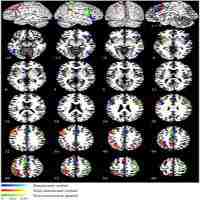

| Abstract | Prior research suggests that conscious face processing occurs preferentially in right hemisphere occipito-parietal regions. However, less is known about brain regions associated with non-conscious processing of faces, and whether a right-hemispheric dominance persists in line with specific affective responses. We aim to review the neural responses systematically, quantitatively, and qualitatively underlying subliminal face processing. PubMed was searched for Functional Magnetic Resonance Imaging (fMRI) publications assessing subliminal emotional face stimuli up to March 2022. Activation Likelihood Estimation (ALE) meta-analyses and narrative reviews were conducted on all studies that met ALE requirements. Risk of bias was assessed using the AXIS tool. In a meta-analysis of all 22 eligible studies (merging clinical and non-clinical populations, whole brain and region of interest analyses), bilateral amygdala activation was reported in the left (x=-19.2, y=1.5, z=-17.1) in 59% of studies, and in the right (x=24.4, y=-1.7, z=-17.4) in 68% of studies. In a second meta-analysis of non-clinical participants only (n=18), bilateral amygdala was again reported in the left (x=-18, y=3.9, z=-18.4) and right (x=22.8, y=-0.9, z=-17.4) in 56% of studies for both clusters. In a final meta-analysis of whole-brain studies only (n=14), bilateral amygdala was also reported in the left (x=-20.2, y=2.9, z=-17.2) in 64% of studies, and right (x=24.2, y=-0.7, z=-17.8) in 71% of studies. The findings suggest that non-consciously detected emotional faces may influence amygdala activation, especially right-lateralised (a higher percentage of convergence in studies), which are integral for pre-conscious affect and long-term memory processing. |